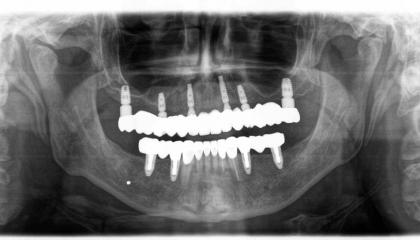

Zirconia bridge on Southern DC Implants

Tooth Replacement